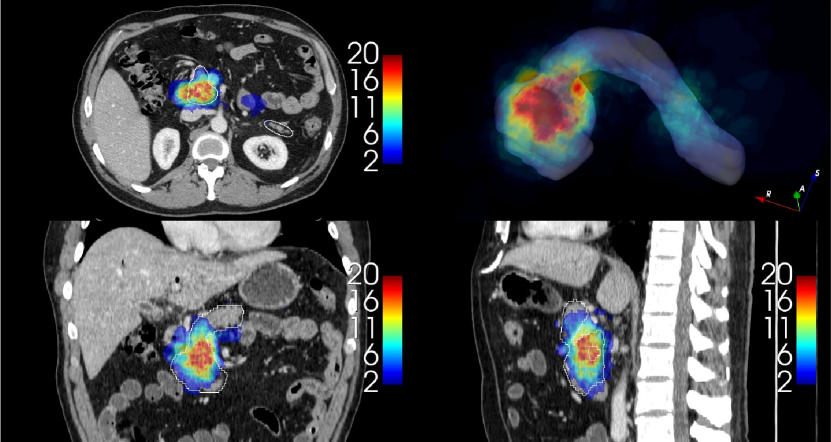

In order to provide an example of the variability of the pancreas parenchyma in terms of size and location, a registration was performed on 281 CTs of the MSD dataset using Elastix software (Klein et al., 2010), adapting inter-subject registration parameters from the study by Qiao et al. (2016) to the CT domain. Subject 29 of MSD was considered a reference image by virtue of its high-quality image and centrality within the range of variations observed in the dataset. A Hounsfield unit (HU) from 100 to 500 was used for all the images to improve the registration process, enhancing bones and brighter abdominal structures. The results are illustrated in Fig. 10. A histogram with the frequency distribution is shown in Fig. 11. It was created by measuring the volumetric distances from the centroid of the pancreas in subject 29 of MSD to the centroids of the pancreas from all other subjects after performing the registration.